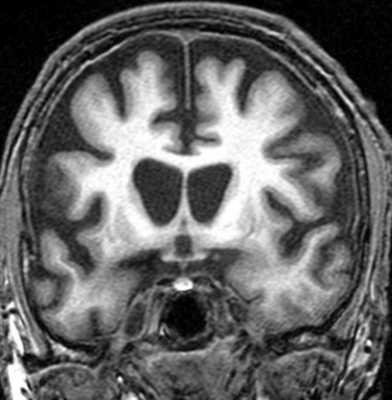

МРТ головного мозга выявляет скопление гемосидерина. Наиболее чувствительны градиентные Т2-взвешенные МРТ. Часто отмечается атрофия червя мозжечка, особенно, видимая хорошо на сагиттальных Т1-взвешенных МРТ.

МРТ головного мозга. Т2-взвешенная аксиальная МРТ через ствол. Тонкое темное кольцо гемосидерина вокруг ствола и в мозжечке. Сидероз головного мозга.